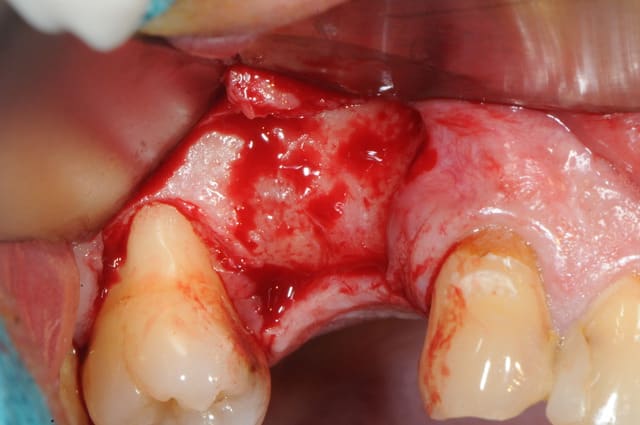

en attendant voici un des deux sinus de ce matin.

MP3 ( chez Pred) en comblement et ROG avec membrane et pins pour palier la forte concavité vestibulaire.

si mais la ROG n'était pas initialement prévue.

je l'ai décidé en cours d'intervention car la dépression osseuse méritait bien une petite augmentation de volume histoire de poser un implant avec un peu plus de nonos autour.